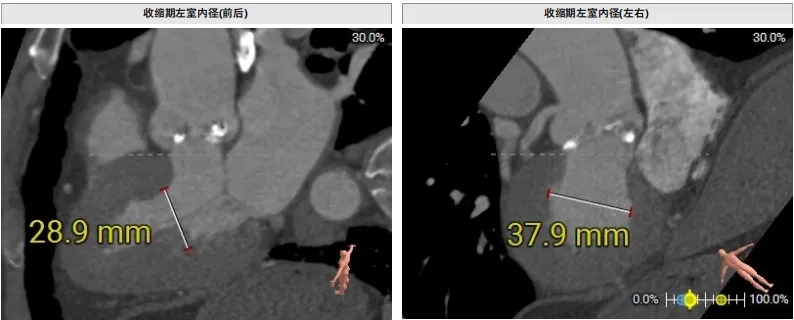

type1型二叶瓣,左右融合,融合嵴见钙化,无冠瓣钙化重,环上结构空间可。左右冠脉开口高度可,结合左右融合,冠脉风险低。瓣环夹角约55°,偏横位心,右无交界无严重钙化融合,系统通过顺畅,同轴性欠佳。收缩期左室内径约29*38mm,舒张期瓣叶疑似关闭良好,反流轻,无冠瓣钙化重。室间隔膜部环下长度约3.4mm,流出道较宽约28.1mm,传导阻滞风险低。双侧入路内径可,股动脉分叉皆在股骨头下缘,未见弓部CT影像,升主无明显扩张。

70男性患者,type1型二叶瓣,主动脉瓣重度狭窄,无冠瓣钙化重,瓣环平均直径27.2mm,LVOT平均直径27.6mm,右冠脉开口高度可,冠脉风险低,瓣环夹角约55°,偏横位心,外周血管入路条件可。经手术团队综合评估后,拟在纯超声引导下以右侧股动脉为主入路行经导管TAVR,术中选择22mm球囊预扩,拟植入29# Evolut PRO瓣膜,初始释放3节瓣架后定位无窦0位,最终控制植入深度3-5mm,根据情况选择是否后扩。手术在中国科学院阜外医院潘湘斌院长团队指导下完成。